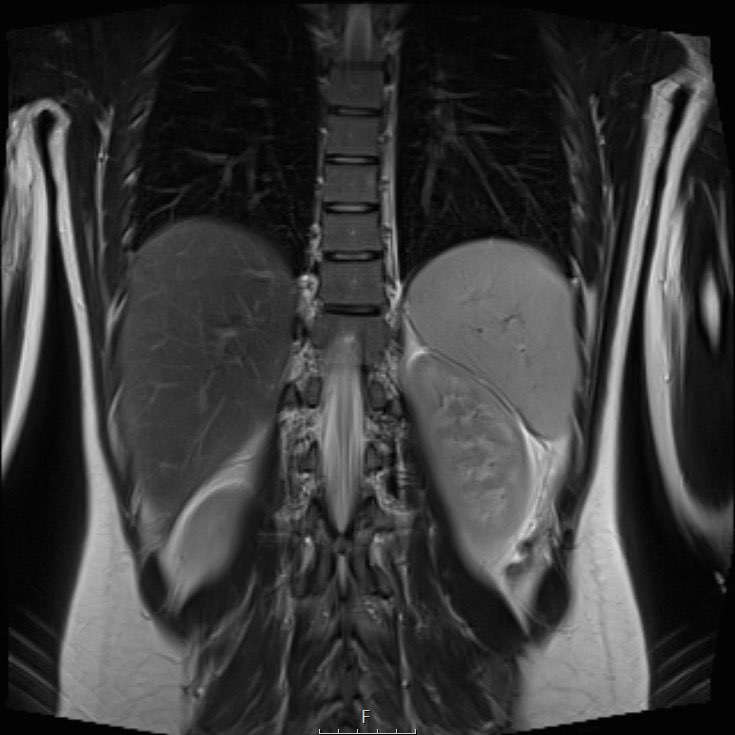

Hình ảnh

U nguyên bào thận ở thận trái của bé trai ba tuổi. Phần còn lại của thận trải dài trên khối u (dấu hiệu “móng vuốt” mũi tên). Khối u khá đồng nhất với một số vùng nang.

Continue with the MRI.

U nguyên bào thận ở thận trái của một bé trai ba tuổi. Khối u thùy đôi nằm ở vùng cực giữa. Có một đài thận giãn ở cực trên (mũi tên).

U nguyên bào thận thường không đồng nhất, với tín hiệu giảm trên T1 và tín hiệu tăng trên T2. Các vùng hoại tử dạng nang thường hiện diện.

Tăng cường tín hiệu sau tiêm Gadolinium không đồng nhất và kém hơn so với sự tăng cường của nhu mô thận bình thường.

Các phần đặc của khối u sẽ cho thấy khuếch tán hạn chế. Xuất huyết thường gặp. Các vùng xuất huyết cũng sẽ cho thấy khuếch tán hạn chế, vì vậy hãy quan sát trên hình ảnh T1 để tìm dấu hiệu chảy máu.

MRI có thể hiển thị rõ ràng huyết khối u trong tĩnh mạch thận và tĩnh mạch chủ dưới, cũng như tình trạng hạch bạch huyết to. Phương pháp này cho phép đo lường khối u một cách chính xác và có thể lặp lại trong các lần khám ban đầu và theo dõi.